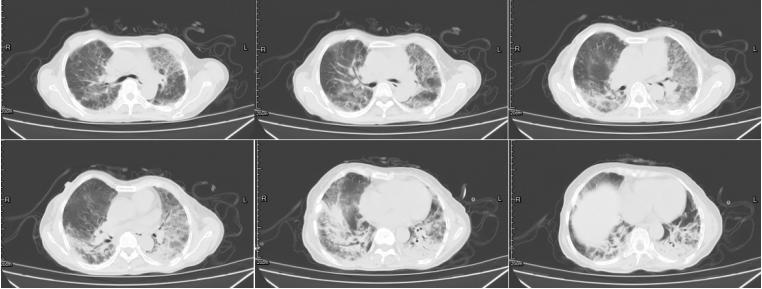

9月1日复查胸部CT可见肺部病灶较前明显改善(图3)

图片

图3 患者胸部CT(2020-09-14)

2021年10月9日胸部CT:两肺渗出,类似间质性改变(图4)

图4  患者胸部CT(2021-09-14)

11月3日复查胸部CT见病变较前明显改善(图5)。11月4日,患者改为鼻导管吸氧。

图5  患者胸部CT对比